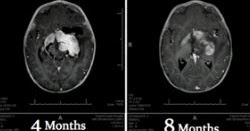

L'huile de cannabis sauve la vie d'un bébé en dissolvant une tumeur au cerveau après que la famille ait rejeté la chimiothérapie

Plutôt que de recourir à la chimiothérapie et à la radiothérapie pour réduire une tumeur au cerveau inopérable, le père d’un enfant de huit mois a opté pour un traitement non conventionnel avec de l’huile de cannabis. Le médecin du bébé, le Dr William était tout d’abord sceptique sur les bienfaits médicinaux de l’huile de cannabis, mais depuis, il y croit vraiment, à la suite du rétablissement remarquable de l’enfant.

Pendant qu’il traitait l’enfant, le père a rapporté qu’ils tamponnaient de l’huile de cannabis sur la tétine du bébé et augmentaient progressivement le dosage. En seulement deux mois, la tumeur au cerveau du bébé avait tellement diminué que l’oncologue pédiatre a jugé que la thérapie conventionnelle était inutile.

Après quatre mois de traitement, la tumeur avait disparu. Au bout de huit mois de traitement, le tissu cérébral était considéré comme normal. Grâce à ces résultats, l’enfant est surnommé « un bébé miracle. »

Le Dr Courtney a ajouté que le succès du traitement signifie que l’enfant n’aura pas à subir les effets à long terme qui surviennent après de hautes doses de chimiothérapie et de radiothérapie.

« Actuellement l’enfant est appelé un bébé miracle, et je dois reconnaître que c’est la réponse parfaite sur laquelle nous devrions insister pour que ce soit la thérapie de première ligne pour tous les enfants avant de se lancer dans tous les traitements qui ont d’horribles effets secondaires à long terme, » a déclaré le Dr Courtney, tel que rapporté par Natural News.